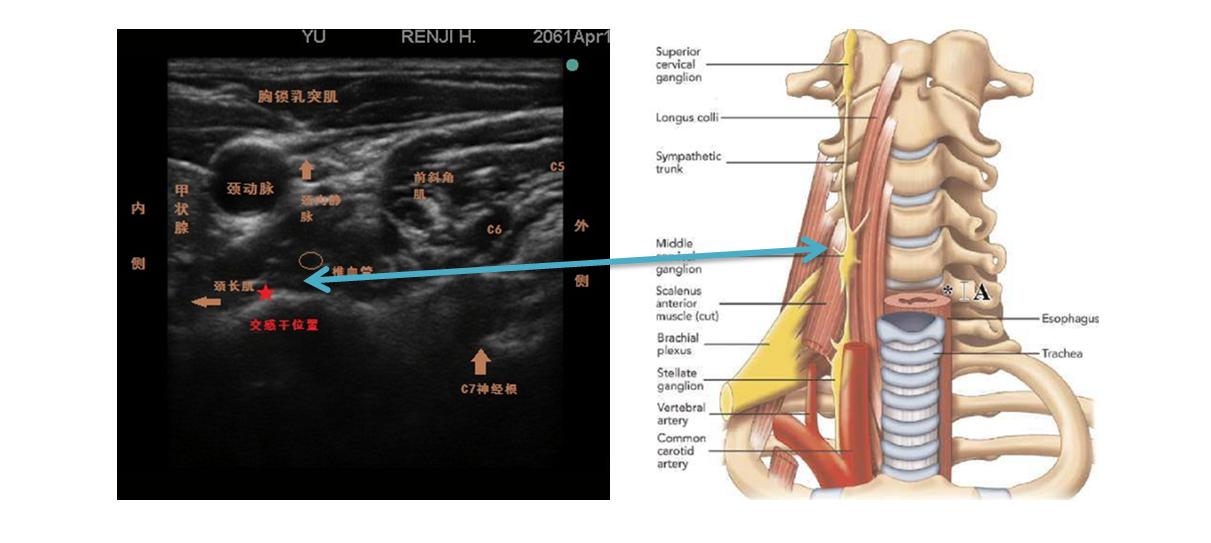

星状神经节阻滞是向颈部包含星状神经节在内的疏松结缔组织内注射局麻药物,可逆性阻滞星状神经节的节前、节后纤维以及所支配的区域头、颈、颜面、上肢的交感神经。

1神经阻滞:星状神经节阻滞属于微创治疗,主要作用于中枢和周围神经,具有调节内分泌系统、自主神经以及免疫系统的功能,可帮助机体维持内环境稳定并保持正常的心血管功能。星状神经节阻滞主要阻断脊髓反射通路,并有效降低交感神经的兴奋性,使肌肉反射性挛缩现象和血管收缩现象消失,致使患者血浆中前列腺素和去甲肾上腺素水平明显下降,从而有效改善局部组织缺血、缺氧及代谢异常现象。改善局部血液循环,解除血管痉挛,改善病变区缺血、缺氧及代谢,减少致痛物质释放,阻断疼痛传导的恶性循环(疼痛-肌肉痉挛-恐惧不安、忧虑-加重带状疱疹神经痛)。